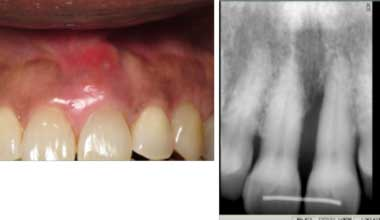

Miss Novice showed radiographic evidence of bone regeneration seven months post LANAP. She completed orthodontics and shows stable bone three years post LANAP.

Miss Novice after the LANAP protocol.